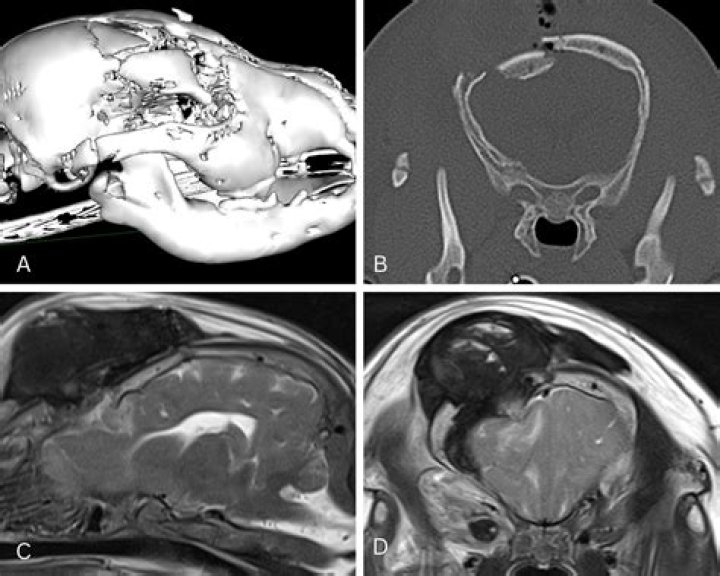

Does an MRI show vestibular neuritis?

Vestibular Neuritis and Labyrinthitis - Diagnosis

Tests to make an accurate diagnosis may include hearing tests and a CT or MRI scan. Your doctor will also check your eyes, which may be flickering uncontrollably. When a patient with vestibular neuritis or labyrinthitis is seen early these eye movement may be observed.